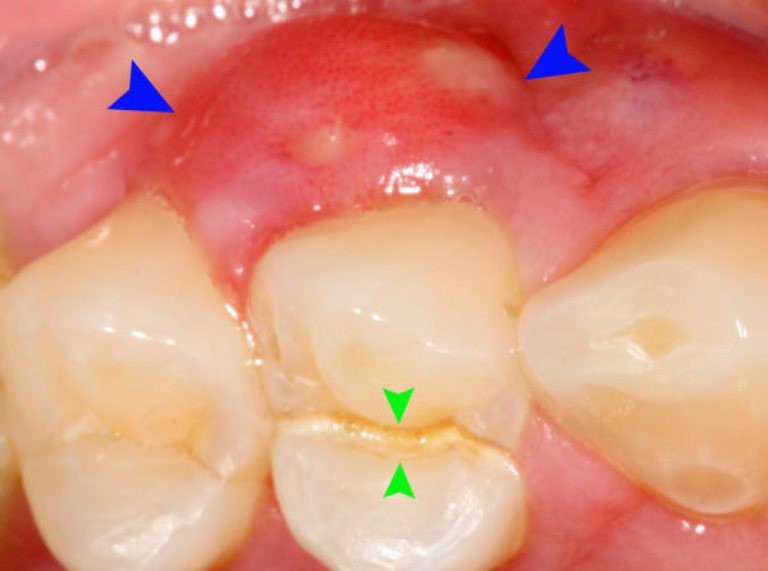

Viêm lợi có mủ (hay còn gọi là

viêm nướu, viêm chân răng có mủ) là bệnh lý răng miệng xảy ra khi lợi bị nhiễm trùng.

Viêm lợi có mủ thường là giai đoạn diễn tiến nặng của viêm lợi thông thường. Răng khôn mọc lệch cũng có thể dẫn đến viêm lợi có mủ.

Dấu hiệu, triệu chứng viêm lợi mủ

Viêm lợi có mủ rất dễ phát hiện với các triệu chứng sau:

Mủ trắng: xuất hiện trên lợi hoặc quanh chân răng

Viêm lợi có mủ có nhiều dấu hiệu nhận biết